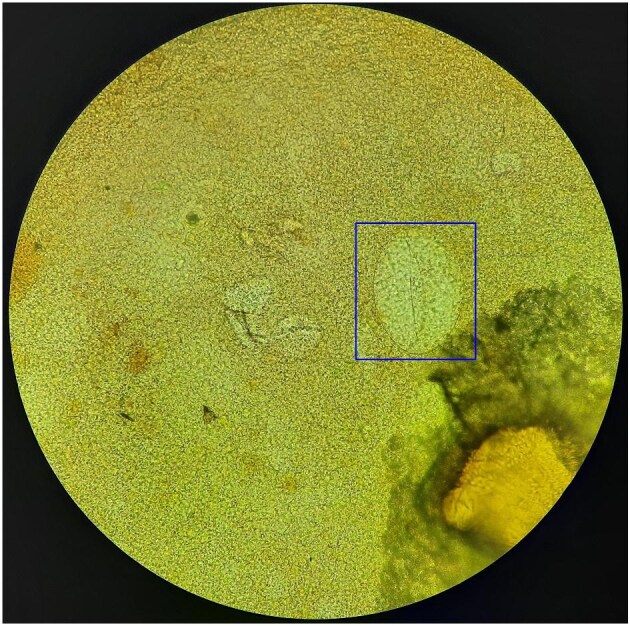

Background: Diagnosis of soil-transmitted helminthiasis and schistosomiasis for surveillance relies on microscopic detection of ova in Kato-Katz (KK) prepared slides. Artificial intelligence (AI)-based platforms for parasitic eggs may be developed using a robust image set with defined labels by reference microscopists. This study aimed to determine interobserver variability among reference microscopists in identifying parasite ova.

Methods: Images of parasite ova taken from KK prepared slides were labelled according to species by two reference microscopists (M1 and M2). A third reference microscopist (M3) labelled images when the first two did not agree. Frequency, percent agreement, κ statistics and variability score (VS) were generated for analysis.

Results: M1 and M2 agreed on 89.24% of the labelled images (κ=0.86, p<0.001). M3 had agreement with M1 and M2 (κ=0.30, p<0.001 and κ=0.28, p<0.001), resolving 89.29% of disagreement between them. The labelling of Schistosoma japonicum had the highest VS (κ=0.487, p=0.101) among the targeted ova. Reference microscopists were able to reliably reach consensus in 99.0% of the dataset.

Conclusions: Training AI using this image set may provide more objective and reliable readings compared with that of reference microscopists.